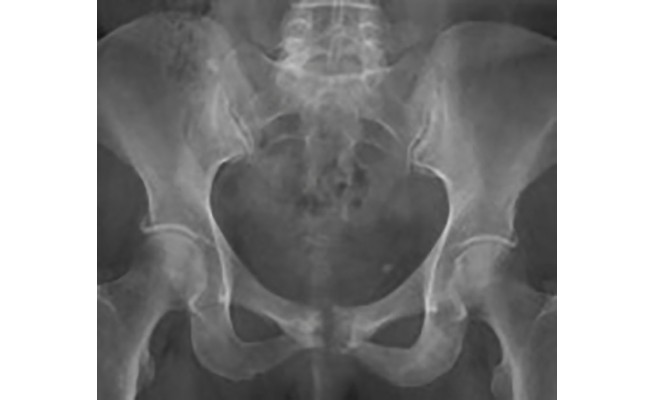

Pubalgie :

Une pathologie délicate